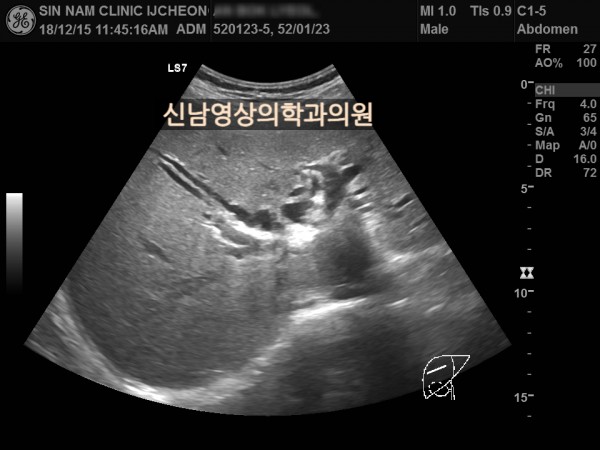

상복부 초음파 적용 사례

본 환자분은 50대 중반의 남성분으로 손가락안이 가렵다는 느낌으로 내원하셨습니다.

담도암과 담관암은 같은 질환을 지칭하는 용어로 간에서 만들어진 담즙이 십이지장으로 이동하는 통로인 담관에 발생하는 악성 종양입니다.

이 암은 간 안에 생기는 간내 담관암과 간 바깥에 생기는 간외 담관암으로 나뉘며, 가장 흔한 증상으로 통증이 없는 황달, 짙은 소변, 옅은 변, 복통, 체중 감소, 소양증 등이 나타날 수 있습니다.

![]()